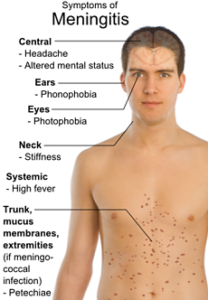

A pesar de las ventajas que supone la comunicación entre la circulación de las arterias carótidas externa e interna, esto también provoca que las infecciones de áreas cercanas a la arteria maxilar evolucionen rápidamente causando graves complicaciones.

Un ejemplo de esto son las infecciones bacterianas de piezas dentales, las cuales cuando son lo suficientemente profundas, pueden permitir el ingreso de bacterias al torrente sanguíneo.

Por medio de la red anastomótica arterial, a través de las ramas colaterales de la arteria maxilar, las bacterias ascienden rápidamente a las estructuras cerebrales ocasionando problemas importantes, como la meningitis, que pueden llevar a situaciones de salud tan delicadas como coma e incluso la muerte.

Otra condición clínica que se presenta debido a la lesión de la arteria maxilar interna es el hematoma epidural. En este caso, la afectada es una de las primeras ramas colaterales, llamada arteria meníngea media. Esta rama se encuentra ubicada por encima de la capa fibrosa que recubre el cerebro, la duramadre.

Cuando una persona sufre un traumatismo en el cráneo, específicamente a nivel del hueso temporal, la arteria meníngea media puede lesionarse y sangrar ocasionando un hematoma que aumenta rápidamente la presión dentro del cráneo.

Un hematoma epidural puede causar la muerte en alrededor del 15 a 20% de los pacientes que acuden con esta condición.